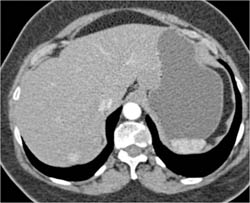

GIST Tumor